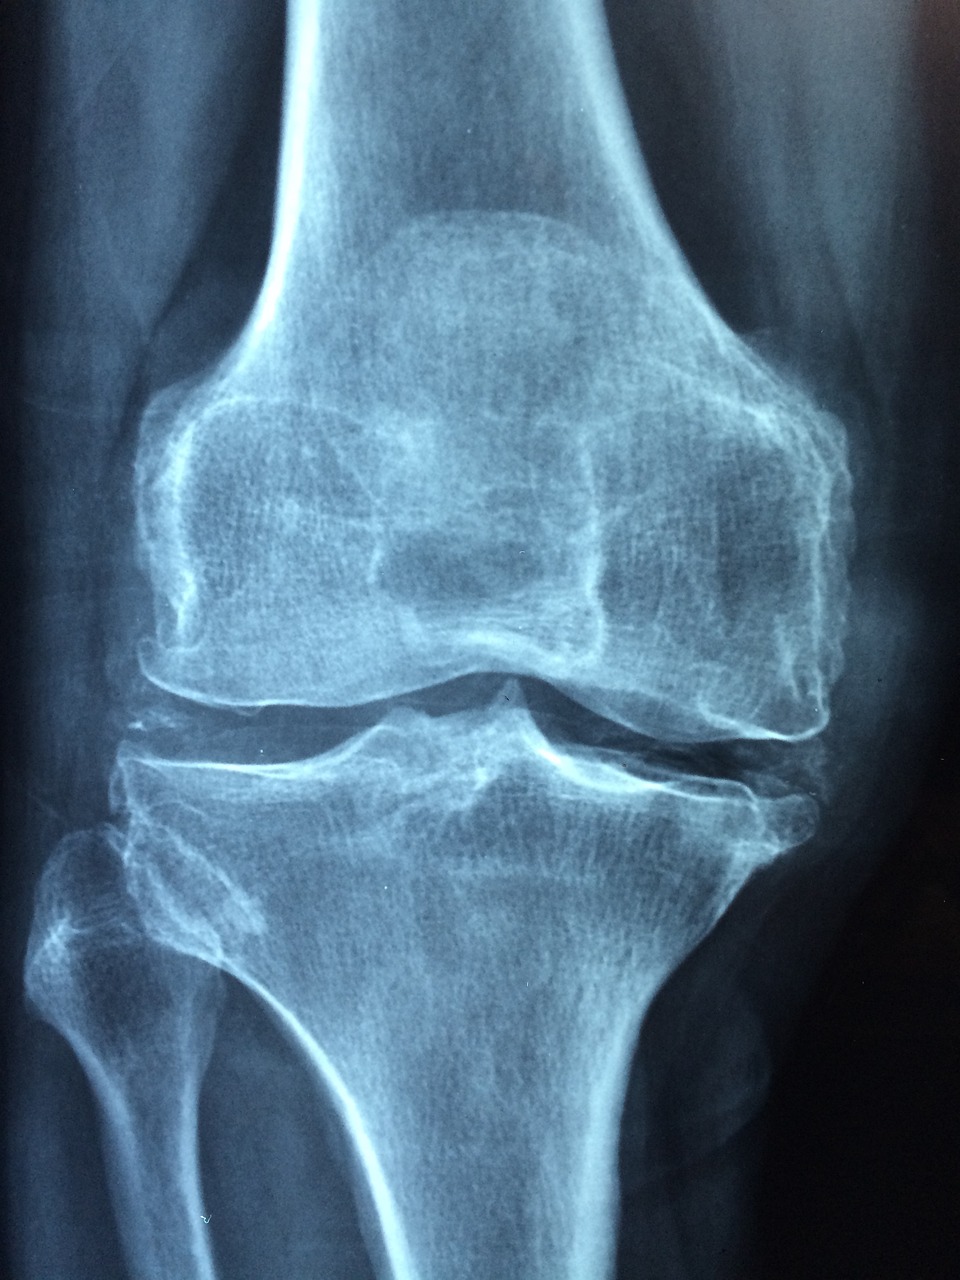

연골은 관절을 보호하는 부드러운 조직으로, 관절의 원활한 움직임을 돕고 충격을 흡수합니다. 연령 증가, 부상, 또는 특정 건강 상태로 인해 연골이 손상되거나 마모될 수 있으며, 콘드로이친은 이러한 연골의 손상을 늦추거나 관절 건강을 개선하는 데 도움을 줄 수 있습니다.

- 관절 건강 증진: 콘드로이친은 연골의 수분 보유 능력과 탄력을 유지하는 데 중요한 역할을 하여, 관절의 윤활을 개선하고 부드러운 움직임을 촉진합니다. 이는 특히 관절염이 있는 사람들에게 통증을 감소시키고 일상 활동의 품질을 향상시킬 수 있습니다.

- 연골 손상 완화: 콘드로이친은 연골 세포의 새로운 성장을 촉진하고 연골 분해를 억제함으로써 연골 손상을 줄이는 데 도움을 줍니다. 이는 연골 마모를 늦추고 장기적으로 관절의 건강을 유지하는 데 기여할 수 있습니다.